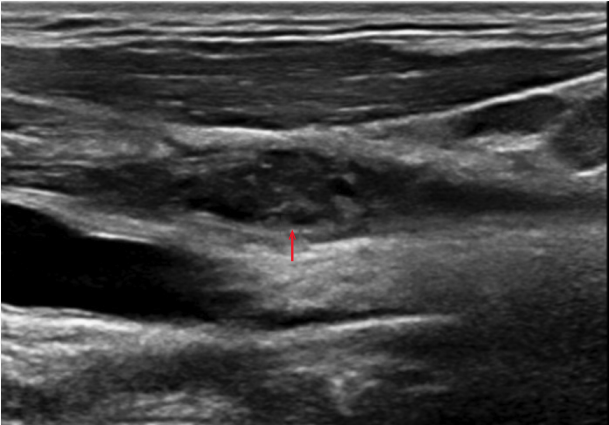

和肿块,其中有空洞形成(图2,3)。颈部左侧超声显示如下(图4)。血培养

图4 左侧颈部超声显示左侧颈内静脉有不可压缩的凝块(箭头)